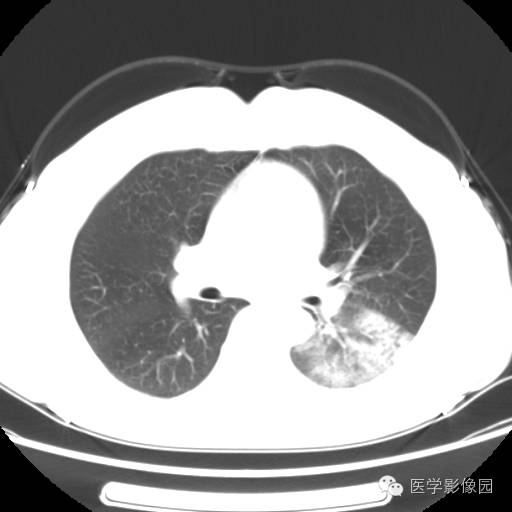

肺叶实变性支气管肺泡癌1例CT影像表现